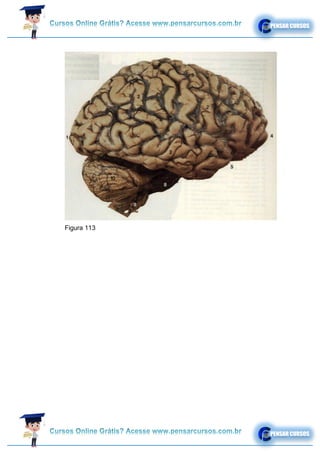

Figura 113